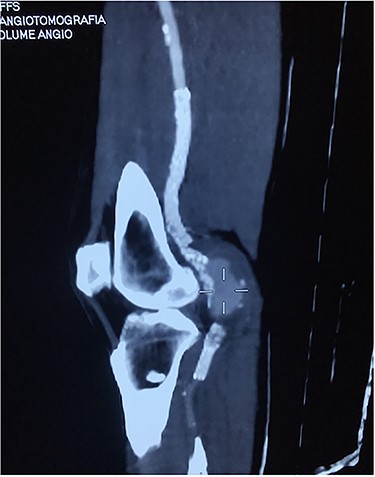

Angiotomography of the popliteal region highlighted the complete stent fracture and a large pseudoaneurysm formation.